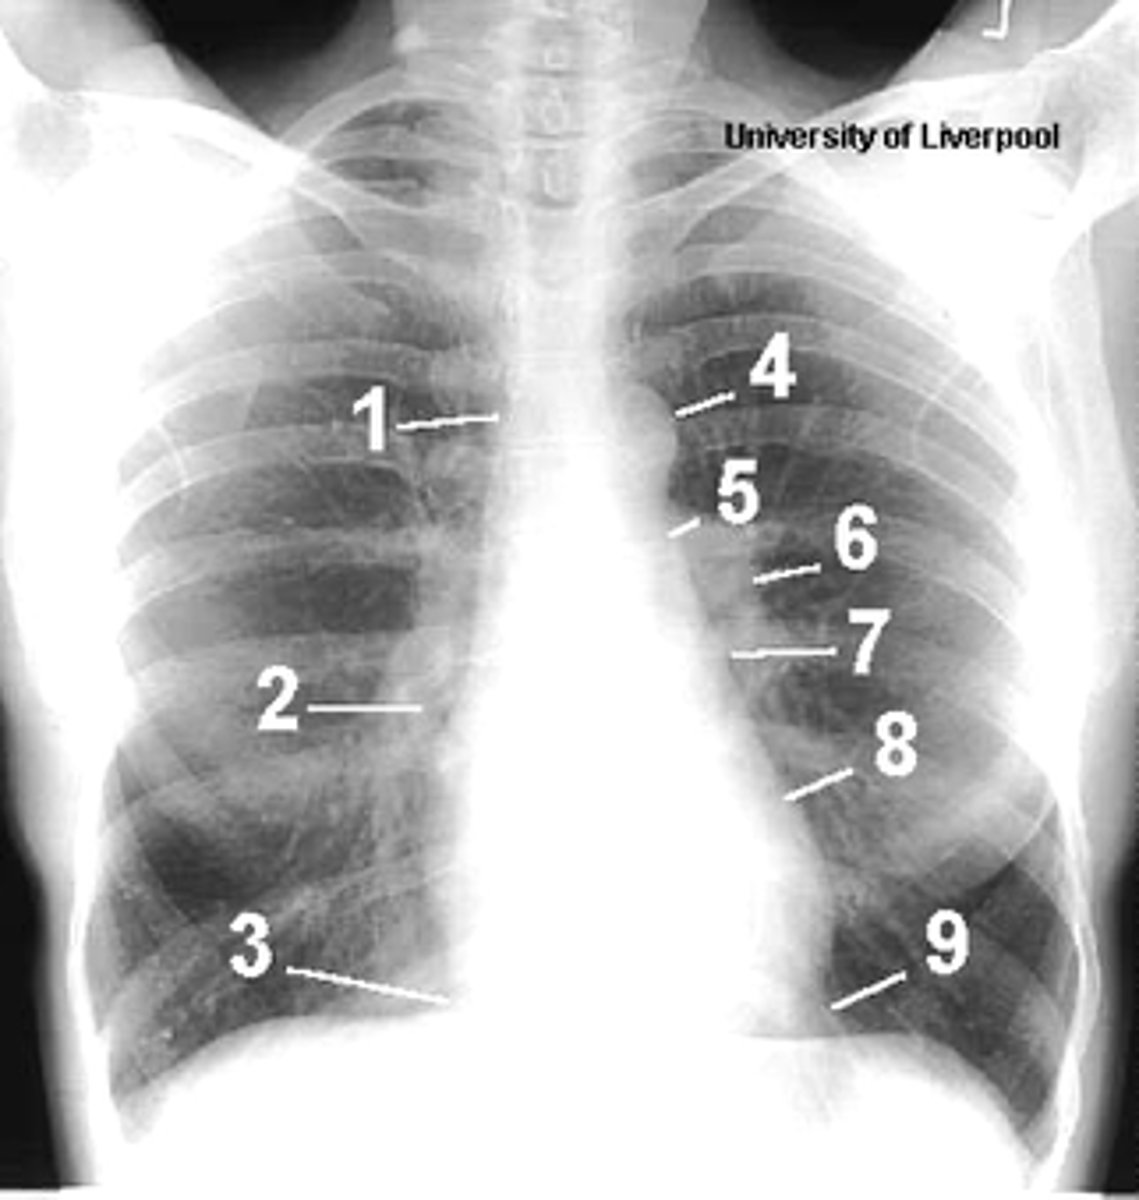

1

superior vena cava

2

right atrium

3

inferior vena cava

4

aortic arch or knob

5

left pulmonary trunk

6

left pulmonary artery

7

left atrium

8

left ventricle

9

left cardiophrenic angle